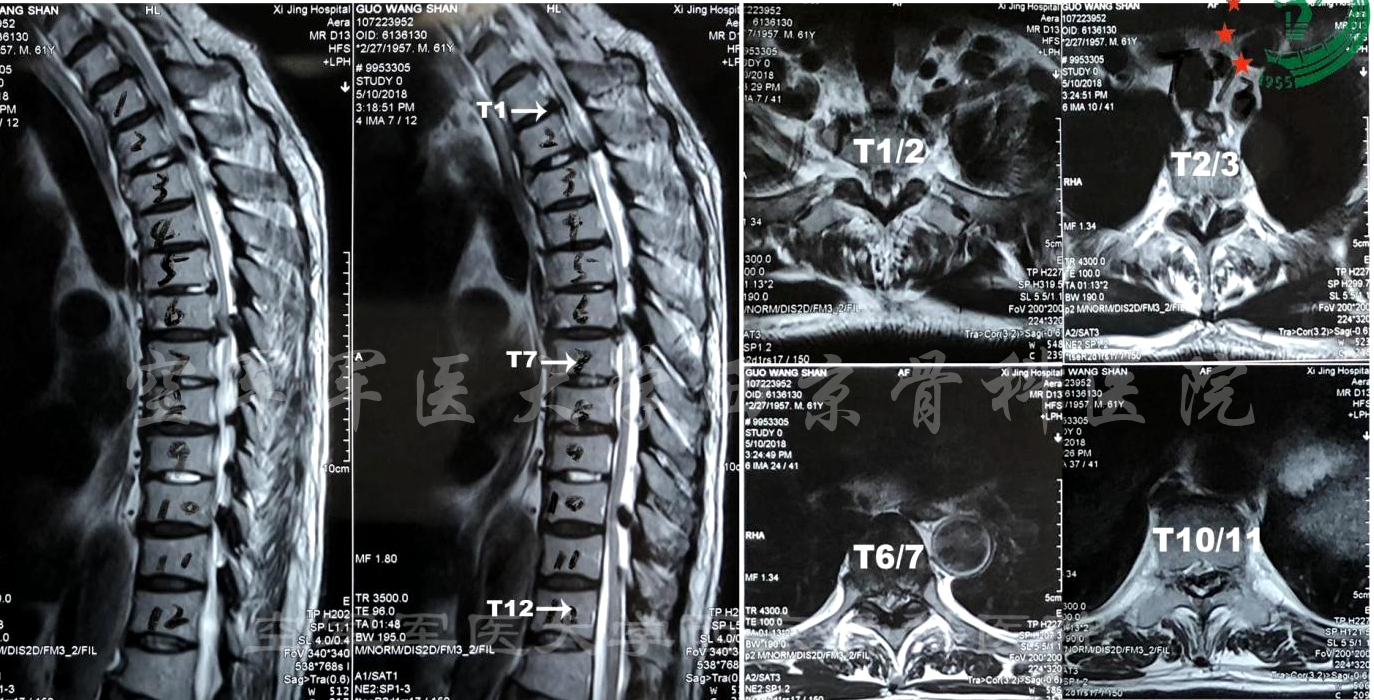

患者:男,61岁

主诉:双下肢麻木、无力11年,加重1月。

既往史:2003年行“颈后路单开门手术”;2010年行“胃癌根治术”;2013年行“腰椎手术”。

轮椅推入病房,脊柱活动度检查不能配合。剑突以下感觉减退。双下肢肌力Ⅱ~Ⅲ级。

诊断:胸椎管狭窄症

术前MRI

术前CT